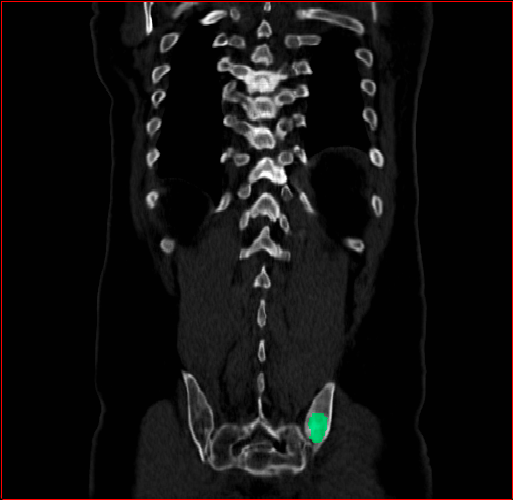

Liver Tumor

0.75×0.75×0.50.75\times 0.75\times 0.5

mm

512×512×768512\times 512\times 768

Refer to caption

Figure 5: MAISI-v2 segmentation-guided results for five types of tumors. We show results for different voxel spacing and volume size to demonstrate the flexibility of MAISI-v2. Different Hounsfield Unit window is used to better show the contrast between tumor and normal tissues.